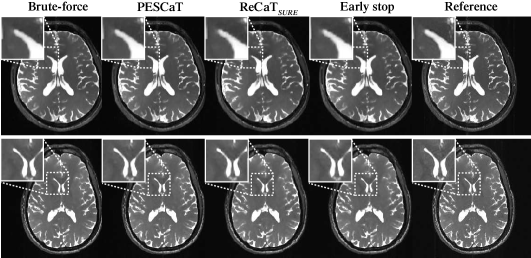

Figure 4: Reconstructions of in vivo bSSFP acquisitions of the brain at R=6. Brute-force, PESCaT, ReCaTSURE, ReCaTSURE with early stop, and reference images are shown in two representative subjects. White boxes display zoomed-in portions of the images. PESCaT achieves significantly improved image quality compared to ReCaTSURE with early stop that was matched PESCaT in terms of the total reconstruction time. Furthermore, PESCaT yields similar image quality to ReCaTSURE and brute-force methods, while also maintaining greater computational efficiency.

Next, PESCaT was demonstrated for in vivo bSSFP, T1-weighted, and ToF imaging of the brain. Representative reconstructions with R=6 for bSSFP and R=4 for T1-weighted and ToF acquisitions are displayed in Figs. 4, 5, and 6. Representative reconstructions of individual phase cycles in the bSSFP dataset, and of cross-sections in the ToF dataset are shown in Supp. Fig. 11. Overall, PESCaT and ReCaTSURE reconstructions perform similar to the brute-force optimized reconstructions. Yet, PESCaT yields slightly lower levels of residual aliasing in comparison to ReCaTSURE, and this difference is particularly noticeable for visualization of small vessels in ToF images (Fig. 6). The improvement in reconstruction quality with PESCaT is more prominent when ReCaTSURE is stopped early to match its reconstruction time to PESCaT.

Quantitative assessments of the in vivo reconstructions are listed in Tables II, III, and IV. For all datasets and R, PESCaT yields the closest performance to the brute-force reconstruction among alternative self-tuning methods. For bSSFP datasets, PESCaT improves PSNR by 1.23±0.29plus-or-minus1.230.291.23\pm 0.29 dB over ReCaTSURE and by 2.55±0.51plus-or-minus2.550.512.55\pm 0.51 dB over ReCaTSURE with early stop (mean±plus-or-minus\pmstd. across three subjects, average of R=2, 4, 6). For T1-weighted datasets, PESCaT improves PSNR by 0.71±0.25plus-or-minus0.710.250.71\pm 0.25 dB over ReCaTSURE and by 1.21±0.43plus-or-minus1.210.431.21\pm 0.43 dB over ReCaTSURE with early stop (mean±plus-or-minus\pmstd. across three subjects, average of R=2, 4). For ToF datasets, PESCaT improves PSNR by 0.72±0.46plus-or-minus0.720.460.72\pm 0.46 dB over ReCaTSURE and by 0.94±0.51plus-or-minus0.940.510.94\pm 0.51 dB over ReCaTSURE with early stop (mean±plus-or-minus\pmstd. across three subjects, average of R=2, 4). Compared to empirically-tuned ReCaTfixed, PESCaT improves PSNR by 0.20±0.37plus-or-minus0.200.370.20\pm 0.37 dB for bSSFP datasets, by 0.45±0.14plus-or-minus0.450.140.45\pm 0.14 dB for T1-weighted datasets, and by 0.91±0.63plus-or-minus0.910.630.91\pm 0.63 dB for ToF datasets (mean±plus-or-minus\pmstd. across three subjects, average of R=2, 4, 6 for bSSFP, average of R=2, 4 for T1-weighted and ToF datasets. Because both methods were allowed to optimize parameters in training subjects, these results suggest that selecting different regularization parameters for each coil/acquisition/subband/level improves reconstruction performance. Compared to PESSPIRiT, PESCaT improves PSNR by 1.16±0.55plus-or-minus1.160.551.16\pm 0.55 dB for bSSFP datasets, by 0.97±0.78plus-or-minus0.970.780.97\pm 0.78 dB for T1-weighted datasets, and by 0.76±0.40plus-or-minus0.760.400.76\pm 0.40 dB for ToF datasets (mean±plus-or-minus\pmstd. across three subjects, average of R=2, 4, 6 for bSSFP, average of R=2, 4 for T1-weighted and ToF datasets). Performance enhancement is even more prominent compared to PESSPIRiT variants that only include sparsity or TV regularization.